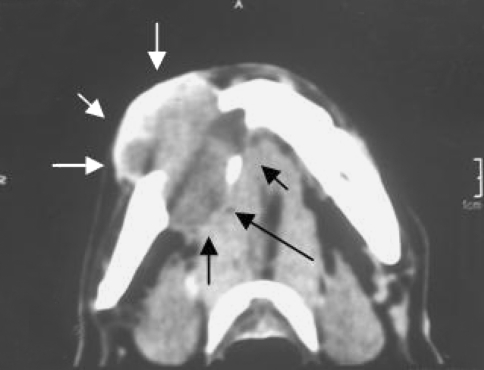

A right lateral oblique radiograph of the mandible showed a single well defined unilocular radiolucent lesion of approximately 2.5 × 2.5 cm in size in the right body with scalloped and irregular margins extending from the 43 to 47 region with thinning and erosion of the inferior border. The roots of 44, 45, and mesial root 46 were resorbed. Occlusal radiograph revealed gross lingual expansion and cortical perforation. A non enhanced axial and coronal computed tomography showed a homogenous expansile lesion affecting the right body of the mandible with thinning and expansion of the buccal cortex with lingual cortex totally destroyed and tumour extending into the soft tissue (Fig. 2). A PA and lateral chest radiograph ruled out presence of any metastatic deposits.

Fig. 2.

Computed tomography